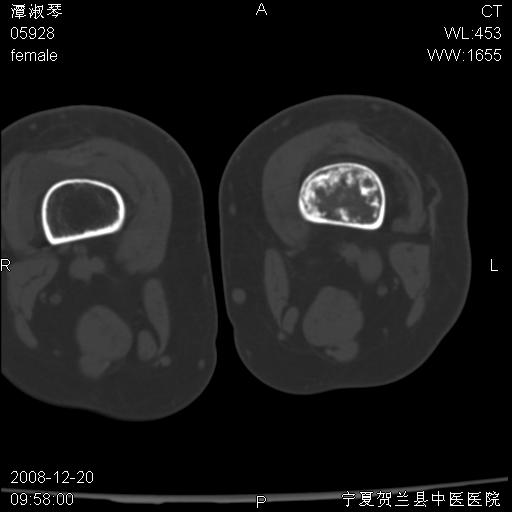

标题: CT17526:请各位看看是啥?

内生软骨瘤?骨梗死?

考虑内生软骨瘤可能性大

考虑-----骨梗死+退变

支持骨梗死,退行性骨关节病,膝关节积液.

考虑骨梗死可能性大

骨梗死可能性大

左侧股骨下段骨瘤

左股骨下段骨梗死。双膝退变。

支持:内生软骨瘤或骨梗死!另:退行性骨关节病,膝关节积液。

左胫骨下端松质骨及髓腔内可见点片状高密度灶,骨皮质无明显膨胀及变薄。病变范围较长。支持骨梗死,退行性骨关节病,膝关节积液